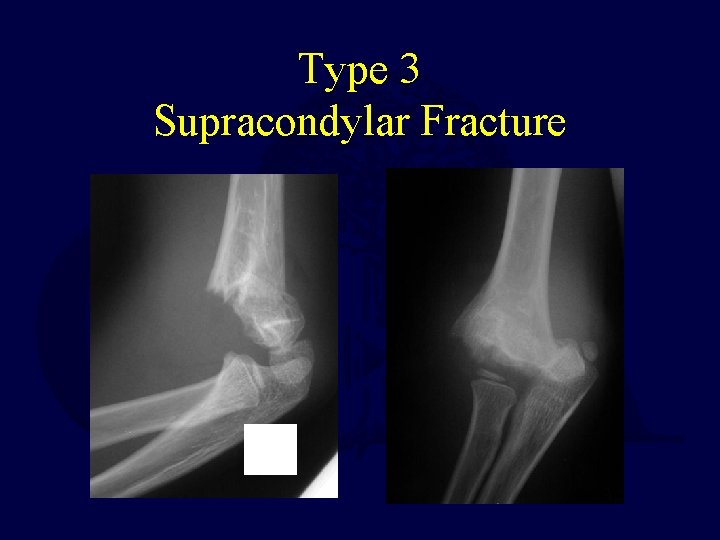

Supracondylar Humerus Fractures Treatment • Type 3 Fractures – These fractures have a high risk of neurologic and/or vascular compromise – Can be associated with a significant amount of swelling – Current treatment protocols use percutaneous pin fixation in almost all cases – In rare cases, open reduction may be necessary • Especially in cases of vascular disruption

Type 3 Supracondylar Fracture

Type 3 Operative Reduction • Closed reduction with flexion • AP view with elbow held in flexed position to maintain reduction.